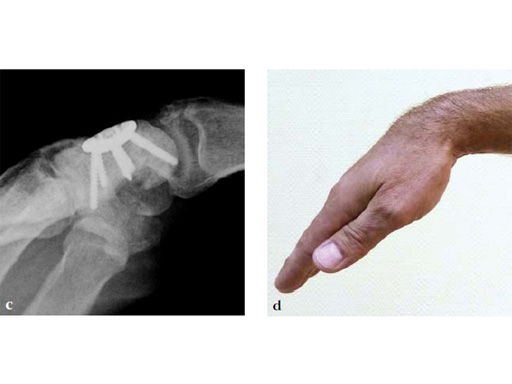

Case 1: SNAC wrist stage 3. Operative procedure and technical details.

Case provided by Ladislav Nagy, Zrich, Switzerland, and Fiesky Nez, Valencia, Venezuela.

Fig 1ab Preoperative x-rays. Notice the midcarpal joint destruction and the DISI deformity of the lunate.

Fig 2ab Dorsal intercalated segment instability correction and K-wire fixation.